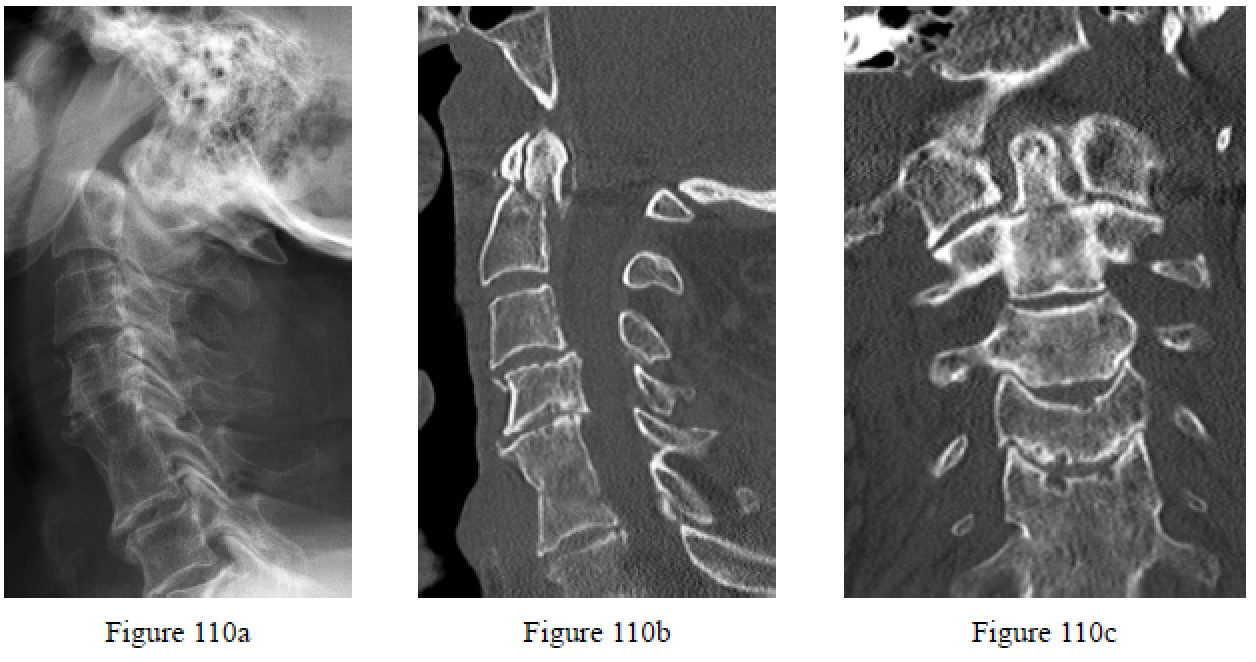

Question 110

Figures 110a through 110c is the upright lateral cervical radiograph and CT scans of an 86-year-old man who has severe neck pain after a fall at home. He is awake, alert, and oriented and has normal neurological examination findings. His medical history is noted for osteoporosis and he is a 60-pack-year smoker. What is the most appropriate treatment?